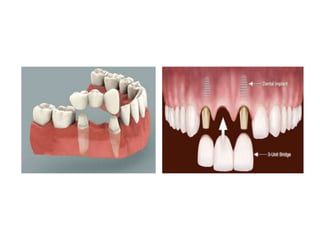

Implant supported restorations

Implant-

supported

restorations

Fixed

Screw-

retained

Cement -

Removable

Implant

overdentures

Hybrid

Fixed implant supported restorations

Screw retained Cement retained